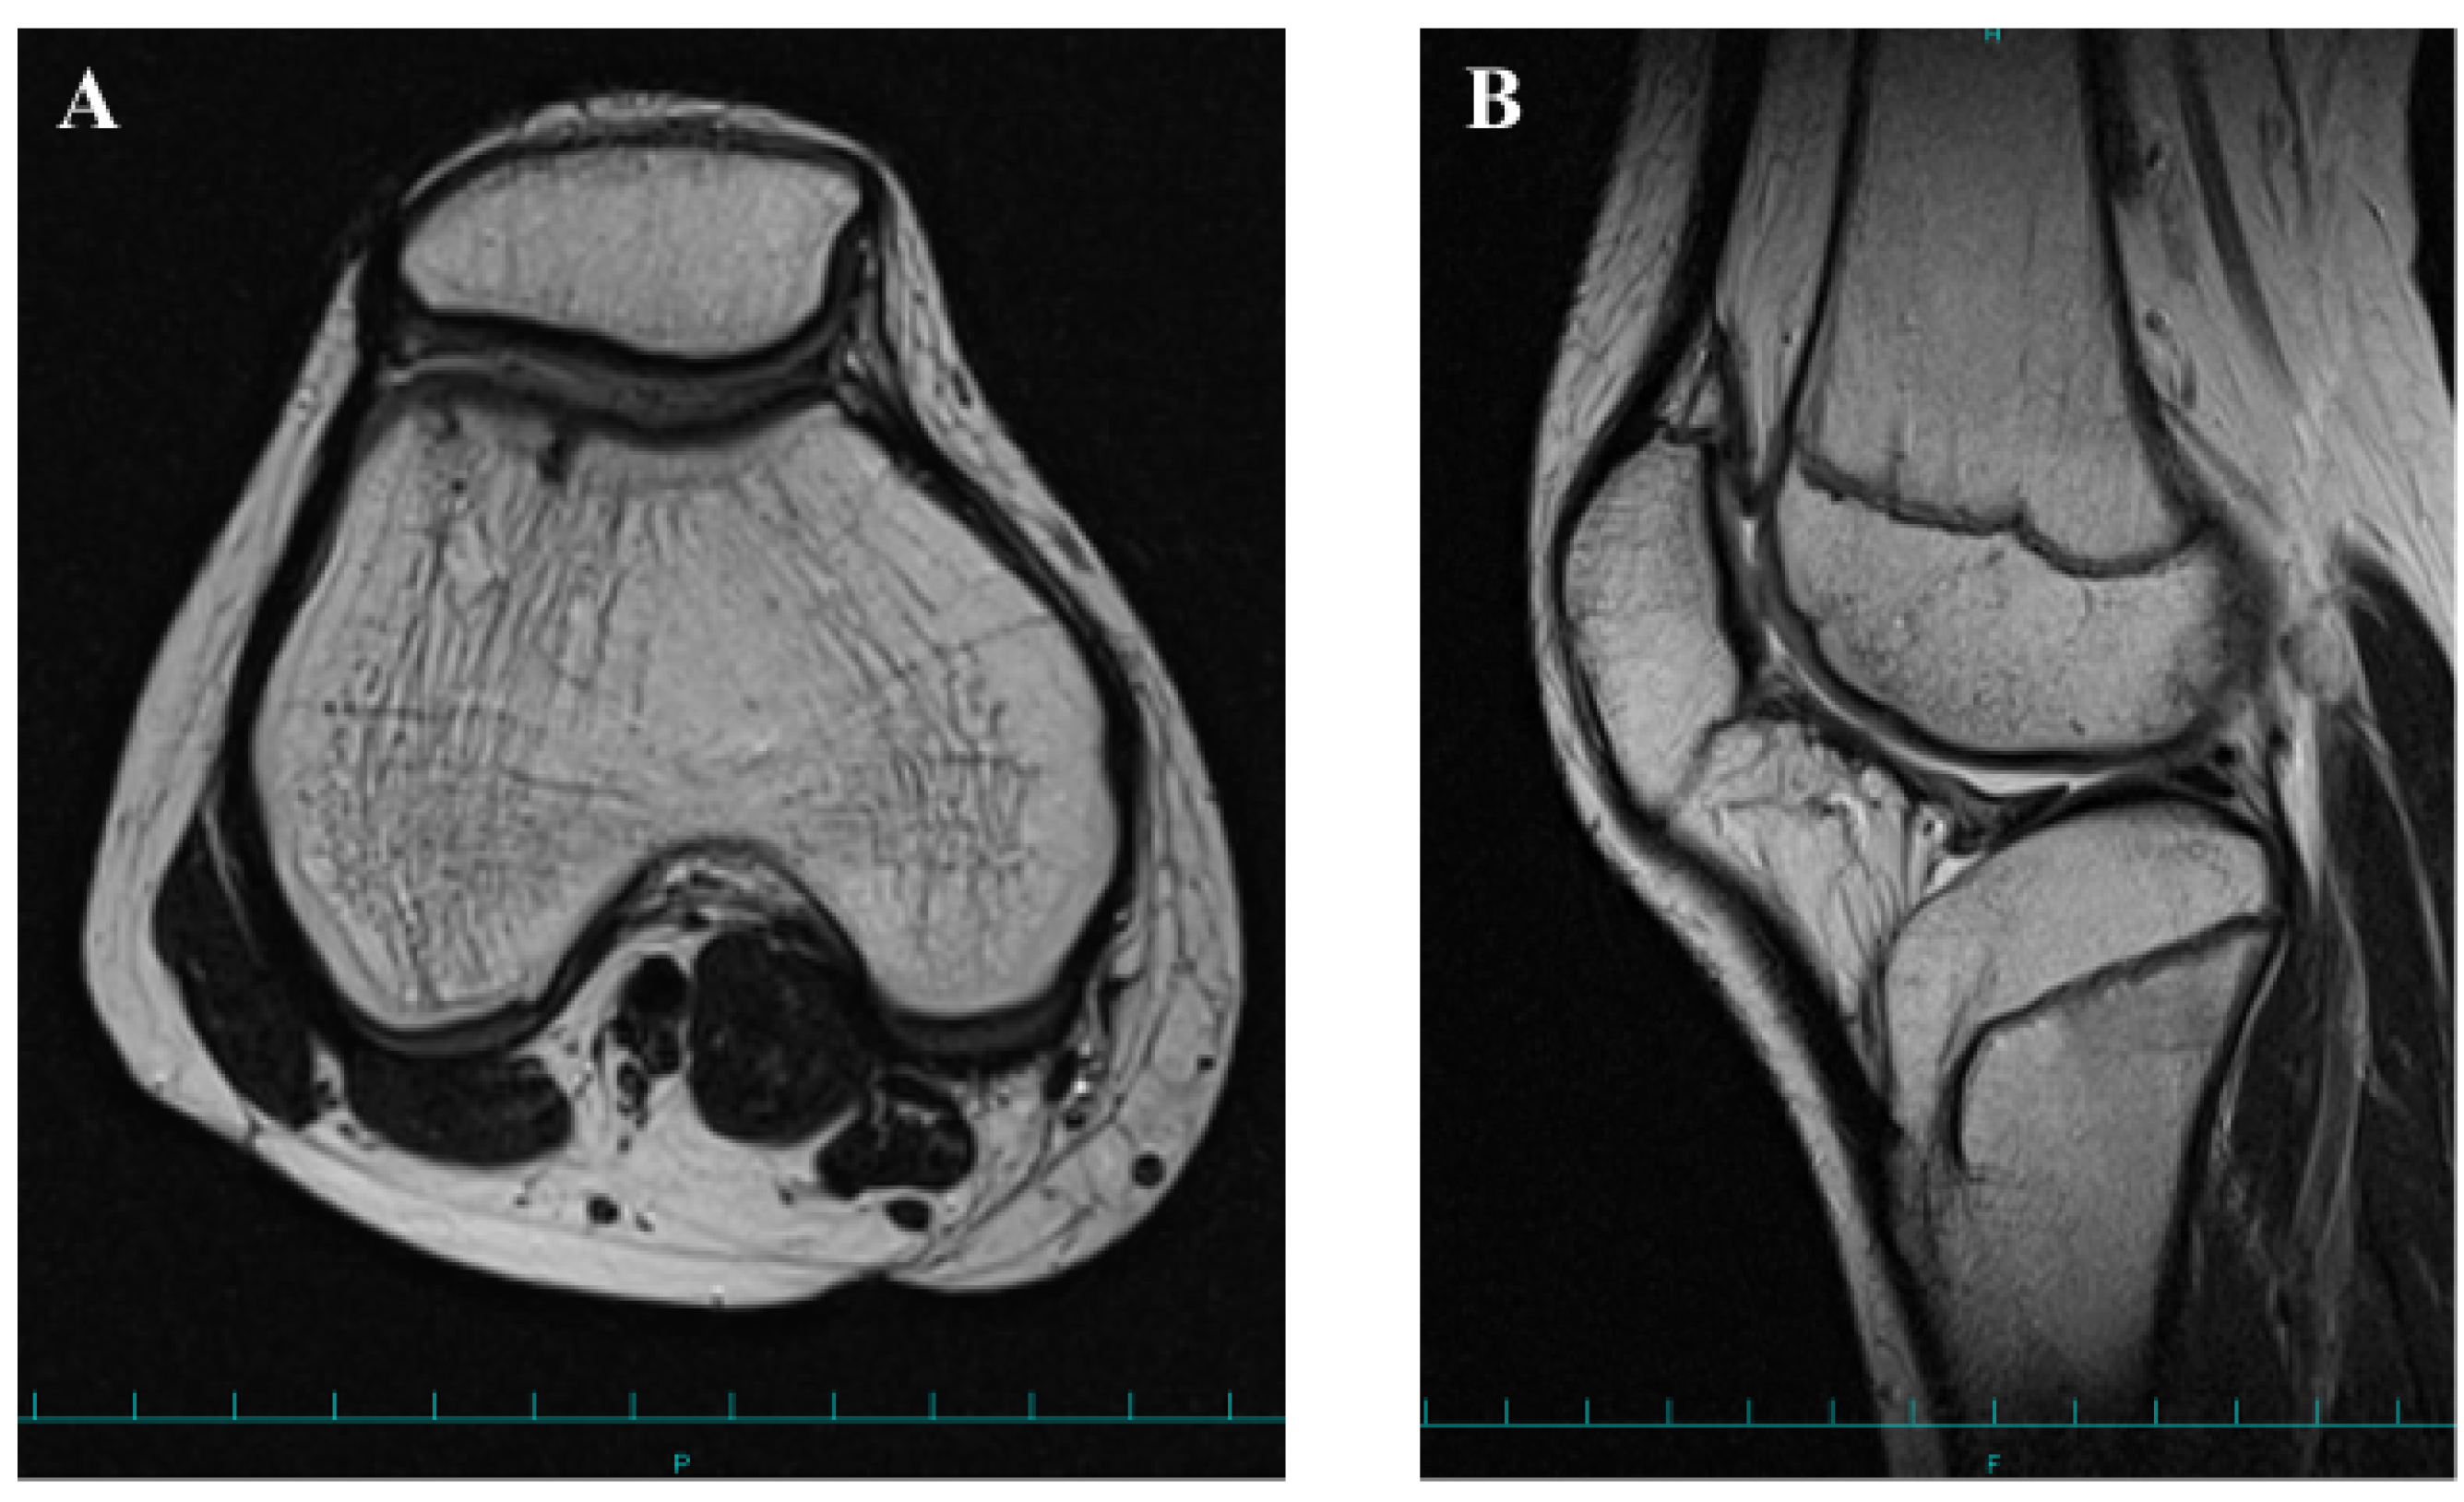

2. Case Presentation